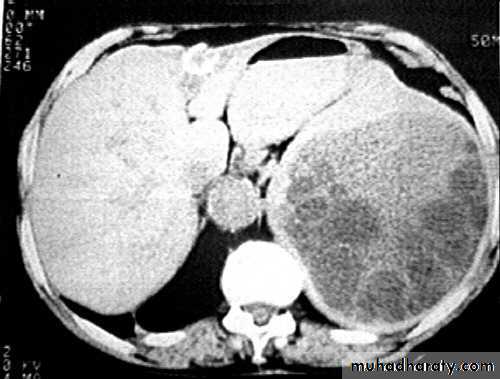

• Echinococcus granulosus: SymptomsSite

SymptomsPathogenesis

abdomen

abdominal distension, ascitisprogressively growing cyst

liver

obstructive jaundice

growing cyst

• Echinococcus granulosus: Diagnosis

• Endemicity• Symptoms

• X-ray and CT scan